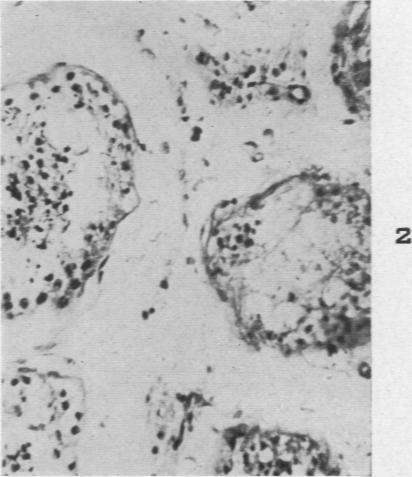

The Histopathology of Acute Mumps Orchitis.

Am J Pathol. 1947 Jul;23(4):637-51.